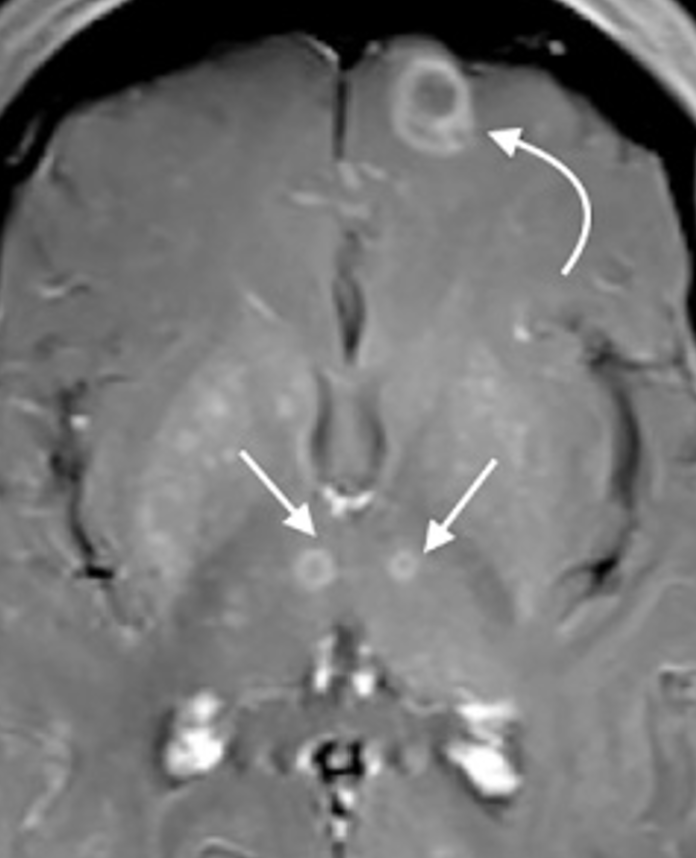

This is the treatment for a patient who is on long-term steroids with the following brain imaging. This patient is an excellent historian who tells you they recently decided to let their cat explore the outdoors where the cat quickly became skilled at catching (and eating) small prey.

What is sulfadiazine and pyrimethamine? BONUS pts for folic acid.